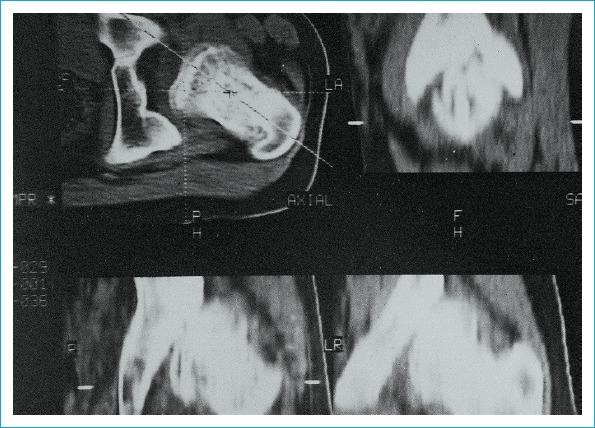

Developmental dysplasia of the hip (DDH) is still one of the biggest orthopedic problems in the world. Global poverty and refugee crises have led to it becoming a greater issue even in developed nations. Early diagnosis and effective treatment of DDH are required to prevent the possibility of arthrosis, limb shortening, pelvic asymmetry, and vertebral scoliosis. In late cases, surgery is the only choice for correction. Direct radiography has been used for many years and continues to have an important role, though ultrasonography is the primary source for early postnatal screening. Although magnetic resonance imaging (MRI) has become an important modality to provide sectional imaging in many cases, in late-period dysplasia, computed tomography (CT) and three-dimensional (3D) CT are preferred because it can more effectively demonstrate the cortical bony structures. The aim of this review was to demonstrate the effectiveness of 3D CT and multiplanar reconstruction based on previous studies.

发育性髋关节发育不良(DDH)仍然是全球最严重的骨科问题之一。全球贫困和难民危机导致即使在发达国家,这一问题也日益严重。为预防关节病、肢体缩短、骨盆不对称和脊柱侧弯的发生,需要对DDH进行早期诊断和有效治疗。在晚期病例中,手术是唯一的矫正选择。直接X线摄影已使用多年且仍发挥着重要作用,不过超声检查是出生后早期筛查的主要手段。尽管磁共振成像(MRI)在许多情况下已成为提供断层成像的重要方式,但在晚期发育不良中,计算机断层扫描(CT)和三维(3D)CT更受青睐,因为它们能更有效地显示皮质骨结构。本综述的目的是基于以往研究展示3D CT和多平面重建的有效性。